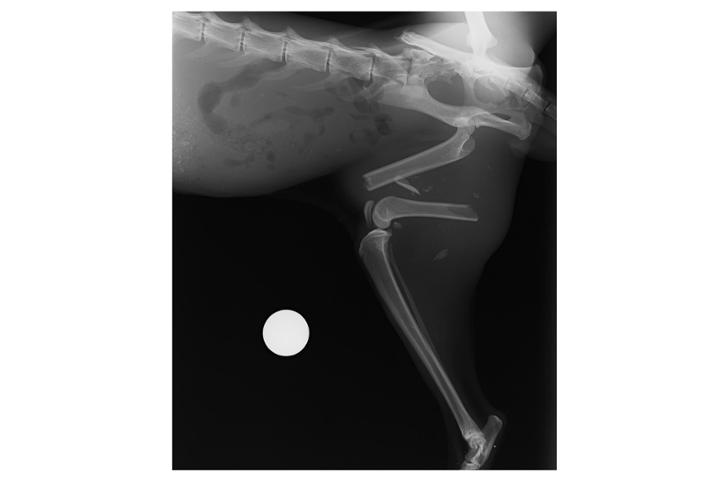

Fijación de fractura de fémur de Axel

Axel es un gatito que vivía en la calle. Nos dieron aviso de que había un gato con mal aspecto y que le pasaba algo en la pata. Estuvimos intentando capturarlo durante varios dias sin éxito, ya que es un gatito desconfiado. Pero al final con paciencia pudimos cogerlo y llevarlo de urgencia a una clínica veterinaria. Allí nos mostraron la gravedad de sus lesiones. Rotura total de fémur, sin otra solución que operación urgente. Pero su analítica era desastrosa, mucha anemia e infección. No sé podía operar hasta que no estuviera más recuperado. Lleva ingresado desde el día 22 de febrero y fue ya operado el pasado jueves 7 de marzo. El presupuesto de la fijación son 685 €, más lo que ascienda su hospitalización. Agradecemos muchísimo quien pueda ayudarnos, Axel nos necesita. ¡Gracias!